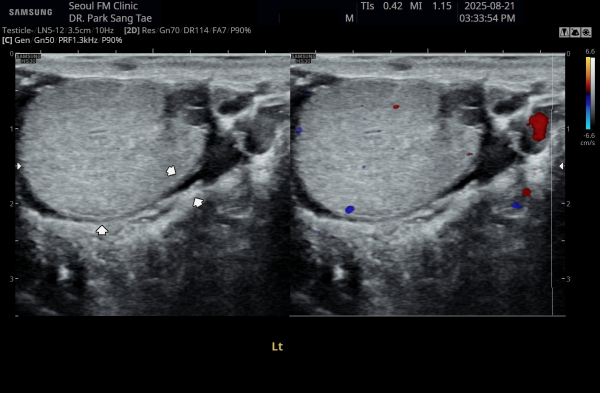

약 8개월후 전립선과 전립선관,사정관,사정관입구,정낭 그리고 정관의 표적 치료후 좌측 정관과 고환의 순환장애가 치료되어

고환의 섬유화가 치료된 초음파 사진입니다.

This ultrasound image, taken about 8 months after starting targeted treatment of the prostate, prostatic ducts, ejaculatory ducts, seminal vesicles, and vas deferens, shows improved circulation in the left testicle. The previous scarring (fibrosis) has healed, indicating that the circulation problem in the vas deferens and testicle has been successfully treated.